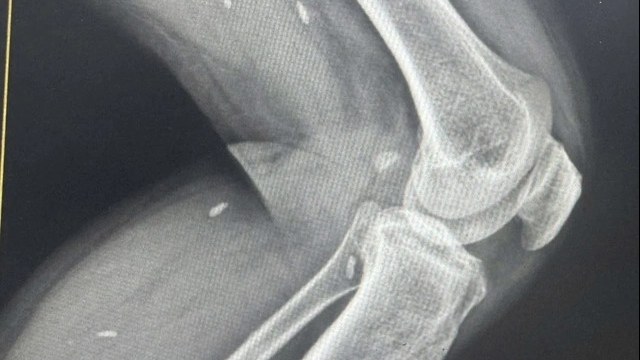

| Ngư dân gặp nạn được sơ cứu trên tàu SAR 412 (Ảnh: CTV) |

Qua quá trình tư vấn y tế, các y, bác sỹ chẩn đoán ngư dân Nguyễn Chín bị tai biến, bị liệt toàn thân, hôn mê và phải được tiếp cận y tế để cấp cứu.

Đến 10 giờ 30 cùng ngày, lực lượng cứu nạn hàng hải đã tiếp cận được tàu QNa 93231 TS, đội ngũ y, bác sỹ cùng nhân viên viên cứu nạn lập tức được triển khai lên tàu để thực hiện sơ cứu tại chỗ cho ngư dân gặp nạn.

Sau khi sơ cứu, ổn định tình trạng, ngư dân Nguyễn Chín được đưa lên tàu SAR 412 để được chăm sóc y tế chuyên khoa.